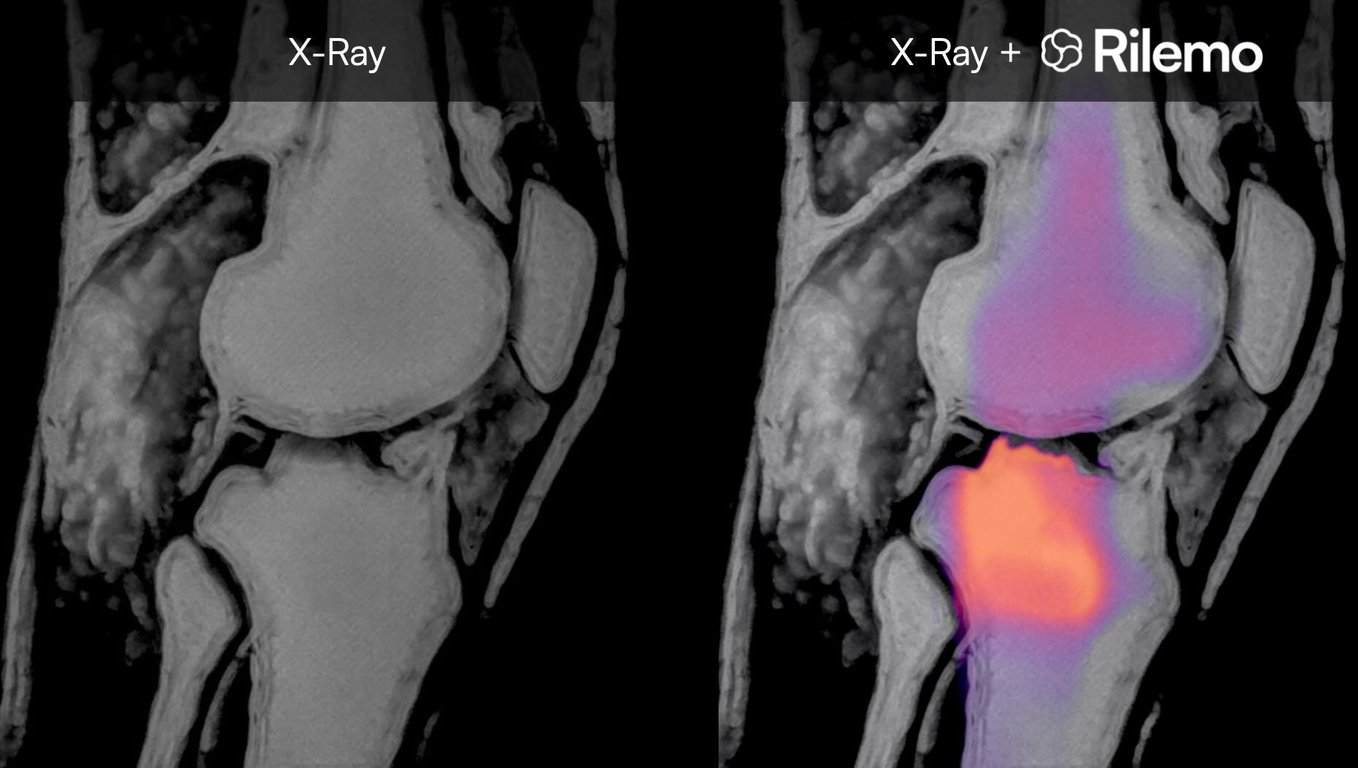

The output is DICOM-compatible (the standard medical imaging format) and can be exported to the hospital PACS (Picture Archiving and Communication System), kept locally on the Bedside Unit's encrypted storage, or fused with existing CT, MRI, or X-ray images for joint interpretation. The fusion approach allows clinicians to read the device's output directly on top of imaging they already know, overlaying fluid-related functional information on a familiar anatomical reference.

- Orthopaedic pathologies - joint effusions, inflammatory conditions, and post-traumatic fluid accumulation.